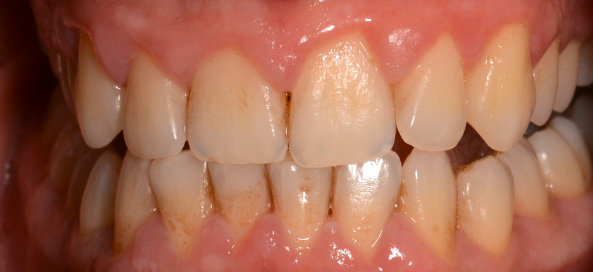

Mulți pacienți tind să amâne vizita la medic, pentru că de cele mai multe ori nu este prezentă senzația dureroasă. Placa bacteriană greu accesibilă și mai ales tartrul pot fi îndepărtate printr-un simplu detartraj cu ultrasunete și un periaj dentar profesional efectuate o dată la 6 luni de către medicul dentist. Spațiile mai greu accesibile cu tartru aderent se vor igieniza mecanic cu instrumente speciale de detartraj: chiurete parodontale și scalare. Prin îndepărtarea plăcii bacteriene și a tartrului și prin menținerea unei igiene corecte, semnele de afectare gingivală vor dispărea, iar gingia își va recăpăta starea de sănătate inițială. Gingivita simplă netratată va evolua în anumite zone ale cavității orale spre boala parodontală. Netratată, aceasta se va extinde treptat la tot mai mulți dinți, având o evoluție cronică și într-un final, după distrucții extinse, se vor pierde dinții. Tratamentul bolii parodontale este mult mai complicat și mai laborios decât al unei gingivite simple, de aceea este foarte important să se intervină în stadii cât mai incipiente ale bolii. (Fig. 5.1.5, 5.1.6, 5.1.7)